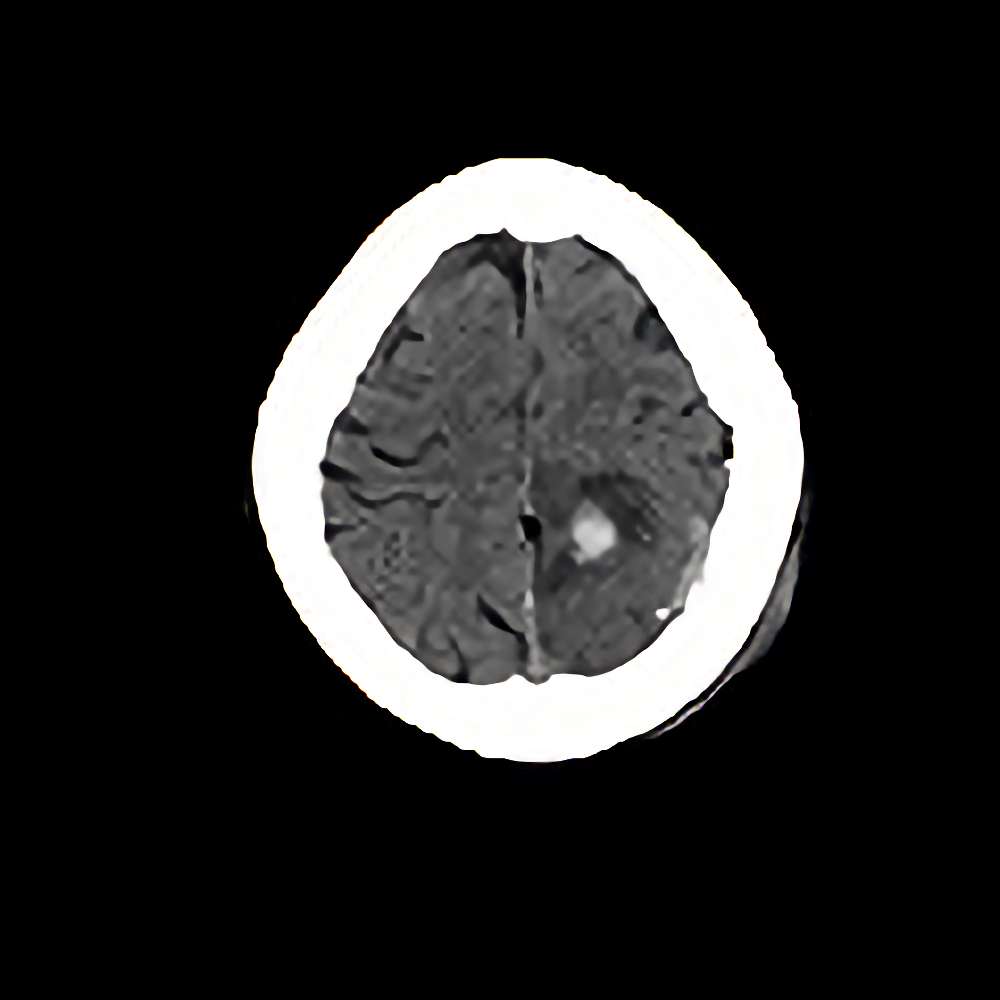

髄膜腫

手術前1

手術前2

手術後

No.’13_68 手術前1

No.’13_68 手術後